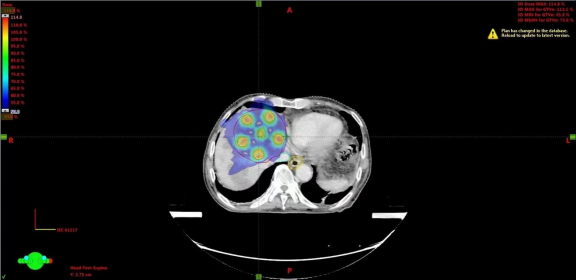

空间放射治疗(SFRT)是一种使用非均匀剂量分布的放射治疗技术,旨在对肿瘤实施大剂量放疗,同时通过在肿瘤体积内交替分布高剂量“峰”和低剂量“谷”,减少对正常组织的损伤。它为复杂肿瘤的放射治疗提供了新的方向,尤其是对难治性、体积庞大的肿瘤有潜在的应用前景。

在治疗过程中,使用TrueBeam平台的精密计划系统,确保了每一剂量都能够精准作用于肿瘤病灶,同时最大限度地减少了对正常肝脏组织的损伤。从治疗计划到实施,整个流程保持高水平的精度和稳定性。